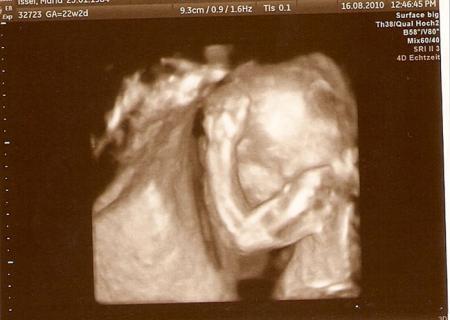

hier ein Profilbild, war schwer zu bekommen da er immer nach hinten gekuckt hat.

Bild zu